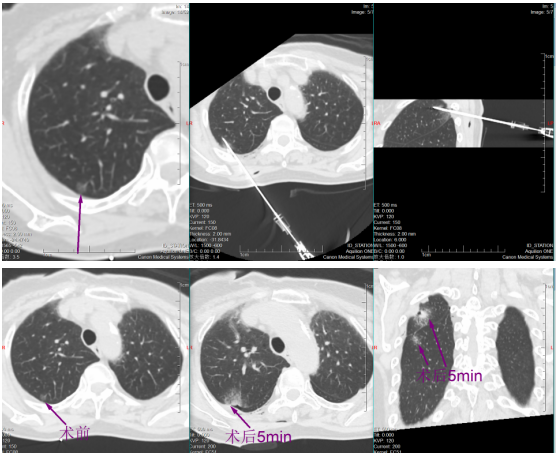

挑战随即开始。帕金森病导致黄女士身体不时微颤,这对需要毫米级稳定的穿刺是巨大干扰。于明川凝神屏息,双手稳如磐石,细微调整针道,在CT的实时引导下,消融针稳稳穿过8毫米的磨玻璃结节,精准停在胸膜前方3厘米处,完美避开胸膜危险区。“开始消融,30瓦一分钟!”随着指令下达,微波消融针开始加热,热量在结节处缓缓扩散,将病灶逐步凝固坏死。黄女士全程清醒,未感丝毫不适。

一分钟后,复查CT显示,结节被一圈磨玻璃密度影完整包裹,这意味着病灶已完全处于烧灼区内,第一枚结节消融成功!

稍后,于明川与冯文汉等团队成员密切配合,向难度更高的第二枚结节发起冲击。这枚结节藏在叶间裂与胸膜构成的狭小夹角内,可操作空间极小,如同在“夹缝中绣花”。按照术前预案,于明川放弃平行进针思路,采用由下而上的特殊进针方式,巧妙避开关键解剖结构。针尖精准抵达结节区域,经过反复测量确认安全后,30瓦功率持续消融一分钟。术中,黄女士的心率、血压始终平稳,未出现任何不良反应。术后CT扫描证实,结节被完全覆盖,烧灼区与叶间裂仅隔几毫米,这毫厘之间的精准,正是生命安全的坚实屏障。